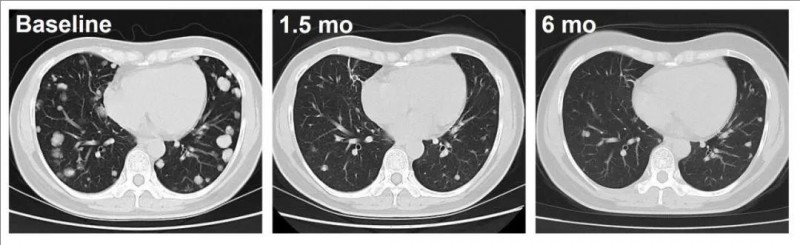

下图展示了两位代表性患者(患者C023、患者C010),经过C-CAR031治疗后,均出现明显反应,肿瘤持续缩小。

C023号患者(DL=4),从治疗1.5个月开始,在肺转移中表现出深度反应,可见肿瘤病灶明显缩小并减少。

▼C023号患者CAR-T治疗前后的影像学对比

肝癌

▲图源“ASCO”,版权归原作者所有,如无意中侵犯了知识产权,请联系我们删除